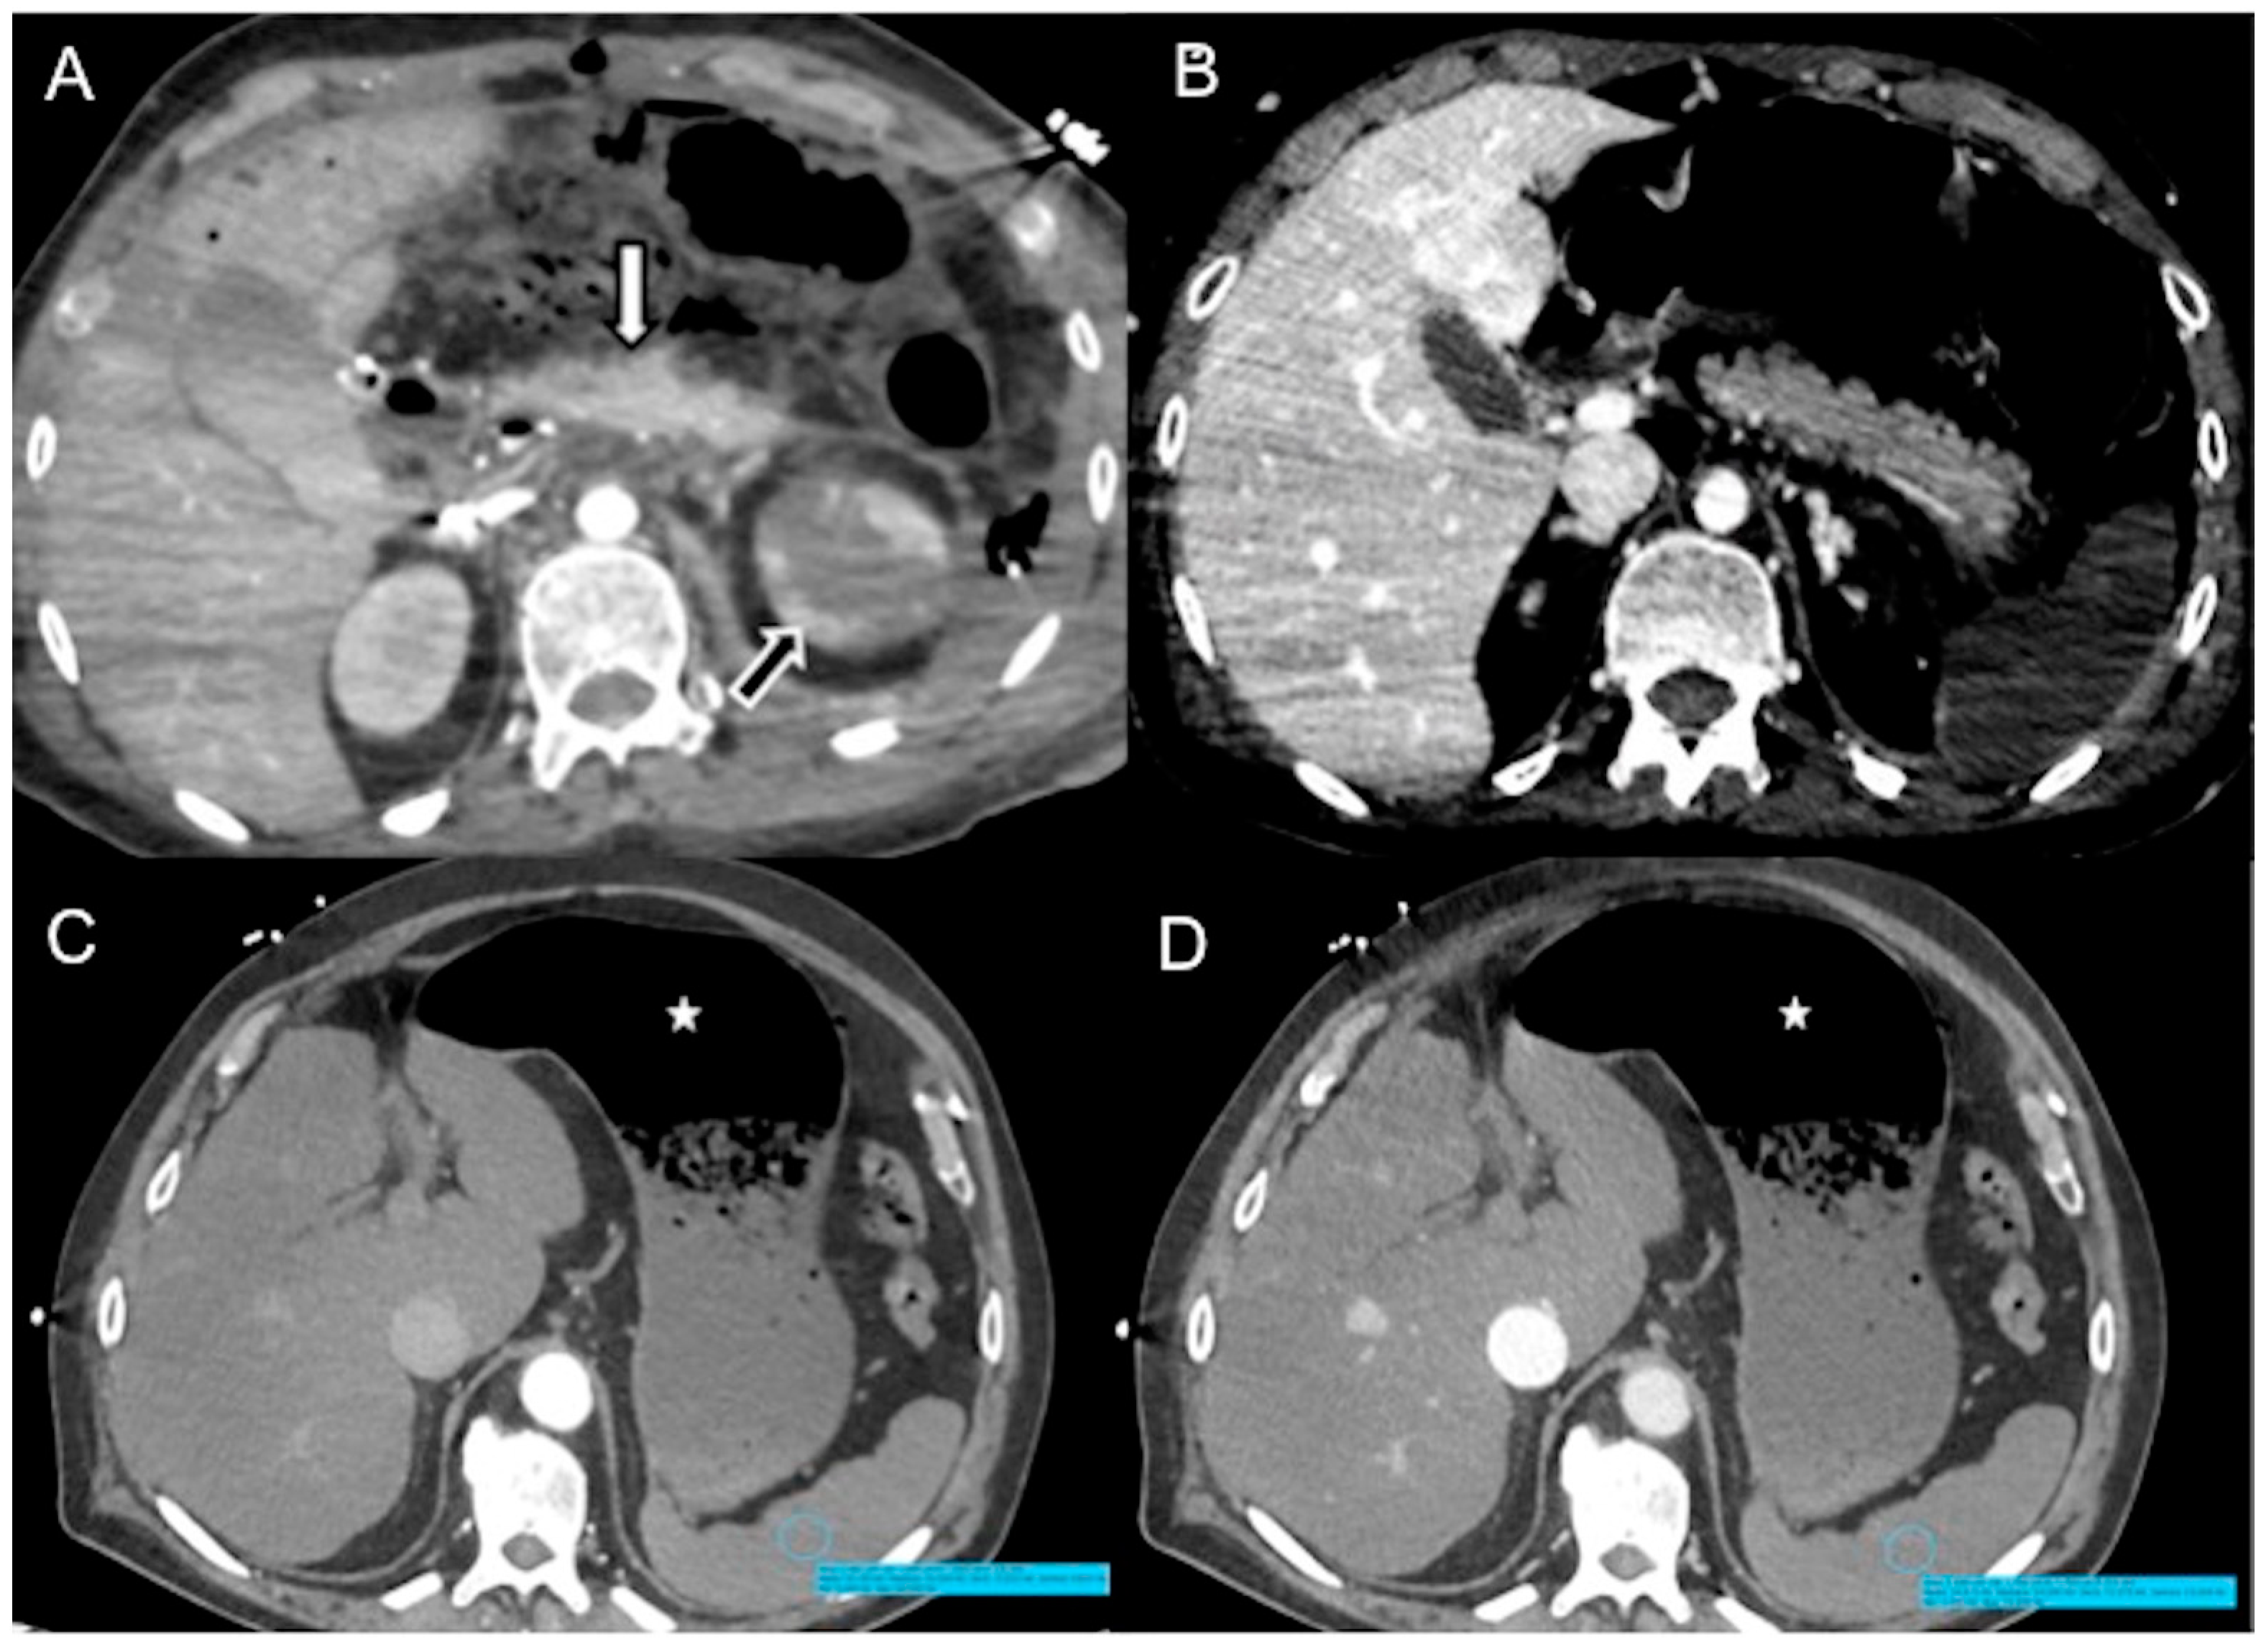

In a normal physiological state, specific gravity has no effect on contrast agent dynamics. In heart failure, CM does not mix with the blood pool and its distribution in the vascular system predominantly depends on its density, injector pressure, specific weight and volume injected [21,39,44]. The dependent layering of injected iodinated CM mainly reflects its higher specific gravity relative to blood in cases of right heart dysfunction and very low cardiac output [47,52]. The consequence is reduced enhancement of the aorta and left-side cardiac chambers with reflux of contrast into the IVC, creating a characteristic horizontal blood-contrast level (“dependent pooling sign” or “IVC contrast level sign”) that could be associated with reflux into the hepatic veins with heterogeneous liver parenchyma enhancement (Figure 3) [18,44,52,66,67].

Figure 3.

CECT axial images of vascular findings in cardiogenic shock. (A) Portal venous phase (delay of 80 s after CM injection) shows IVC contrast level sign (arrow) as well as heterogeneous hepatic enhancement (asterisk) in a 65-year-old man with myocardial infarction and imminent cardiac arrest. (B) Portal venous phase (delay of 85 s after CM injection) shows IVC contrast level sign (arrow) and regurgitation to the right renal vein (empty arrow) in a 63-year-old man with hypotension and acute severe reduction in cardiac index. In comparison to Figure 1D, note the aorta opacification. (C) Portal venous phase (delay of 85 s after CM injection) shows IVC contrast level sign with CM reflux into hepatic VI and VII segments (empty arrow) and (D) contrast level in portal trunk (arrow) in a 68-year-old man with myocardial infarction.